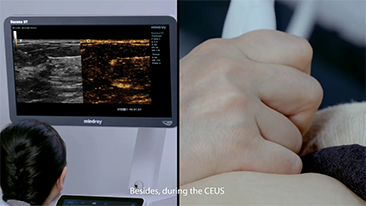

??? ?? ??? ?? ???? ? ??? ?? ??? ?? ??? ??? ??? ???. ???? ??? UWN+ ?? ?? ??? ?? MI??? ??? ??? ?? ?? ??? ?? ?? ?? ???, ?? ?? ?? ???? ??? ? ????.